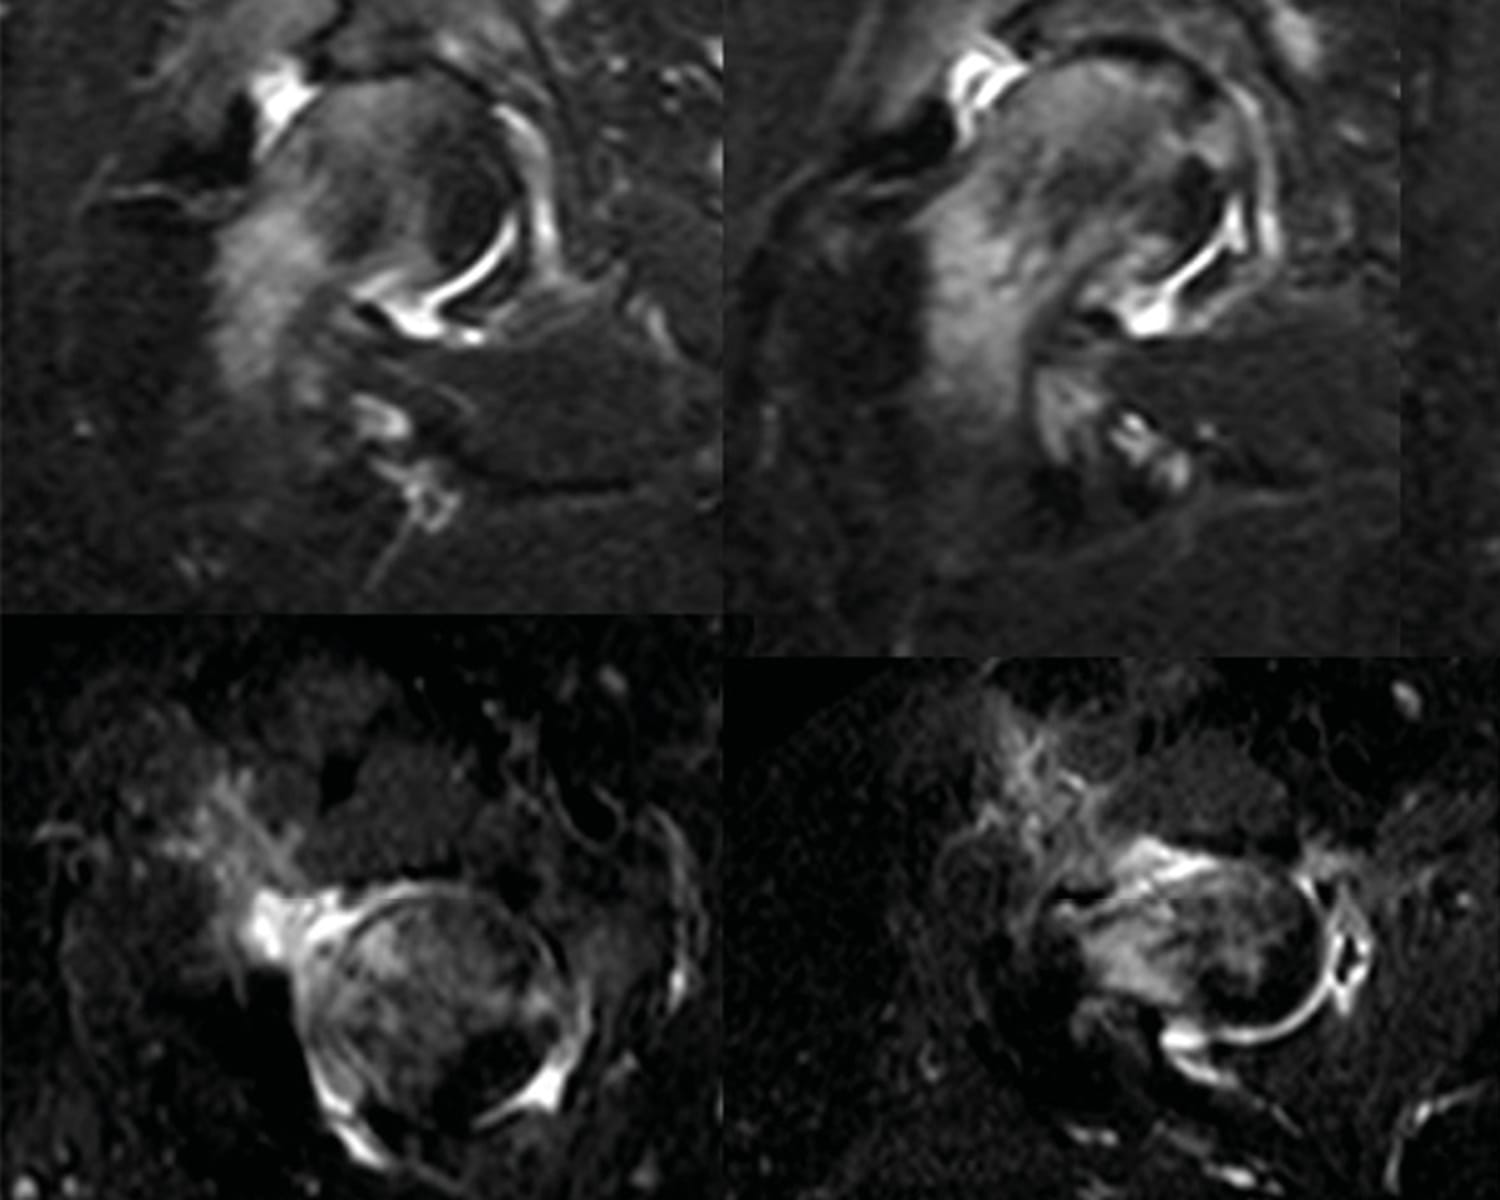

The clinical contributions in this issue address two principal domains. Musculoskeletal infection is examined through a case report on septic arthritis of the native hip caused by Granulicatella adiacens, complemented by a literature review, and a case series investigating surgical options and outcomes in calcaneal osteomyelitis. The issue further addresses revision of total hip arthroplasty, presenting an epidemiological multicentre analysis of 963 patients in France alongside an evaluation of dual mobility systems as a reconstructive strategy in revision settings.